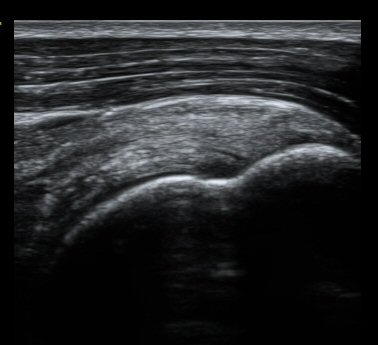

ȸÀü±Ù°³°£°Ý ³»Ãø Ⱦ´Ü¸é°Ë»ç¿¡¼­ °üÂûÇÑ °ß°©ÇÏ±Ù°Ç »óºÎ Á¾´Ü¸é°Ë»ç¿¡¼­ ¹Ì¼¼ÇÑ °£±ØÀÌ

°üÂûµÊ(±×¸² 3, 4). °ß°©ÇÏ±Ù°Ç È¾´Ü¸é°Ë»ç¿¡¼­µµ °ß°©Çϱٰdz» °£±ØÀÌ °üÂûµÊ(±×¸² 5).

±Ø»ó°Ç Á¾´Ü¸é°Ë»ç¿Í Ⱦ´Ü¸é°Ë»ç¿¡¼­ ±Ø»ó°Ç³» ¹Ì¼¼ÇÑ °£±ØÀÌ °üÂûµÊ(±×¸² 6, 7, 8).